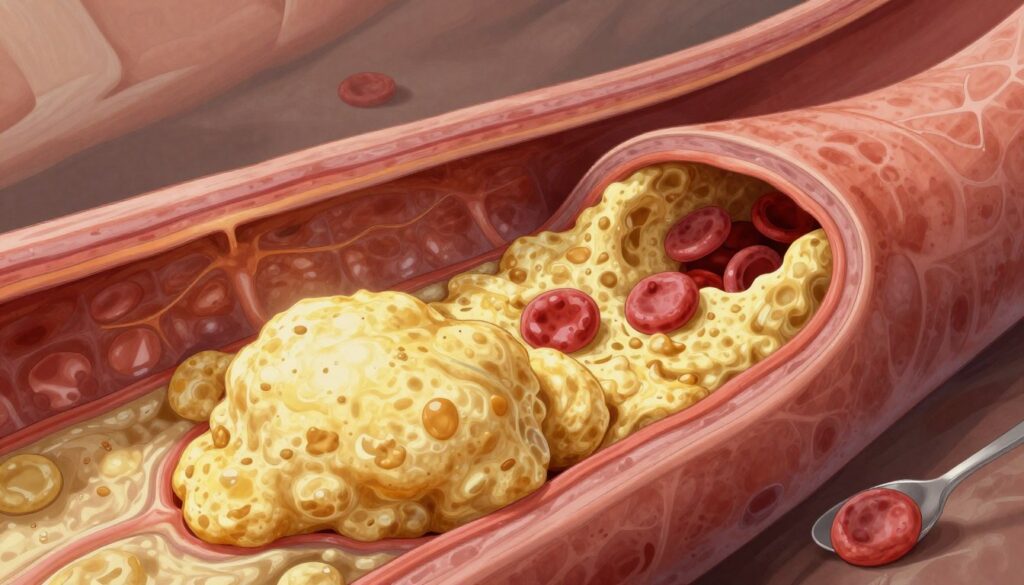

Understanding the Mechanics of Arterial Plaque Buildup

What is Atherosclerosis?

Atherosclerosis means your arteries get clogged with fatty stuff. It starts when cholesterol particles stick to your artery walls. Your body sees this as a threat and sends white blood cells to fight it.

This fight creates inflammation. Over time, cholesterol and immune cells build up, forming plaque. This buildup can block blood flow to your organs.

The Progression of Artery Narrowing

As plaque builds up, your blood vessels get smaller. This artery narrowing makes your heart work harder. At first, the plaque is soft and unstable, which is risky.

If these soft plaques burst, your body tries to heal by forming blood clots. These clots can block blood flow, causing emergencies. Knowing how atherosclerosis works helps you see why it’s crucial to act early and live healthily.

Strategies to Effectively Block Arteries from Developing Plaque

You can’t remove plaque that’s already there, but you can stop it from getting worse. By making consistent lifestyle changes and following medical advice, you can keep your blood vessels stable. This is the best way to block arteries from getting worse over time.